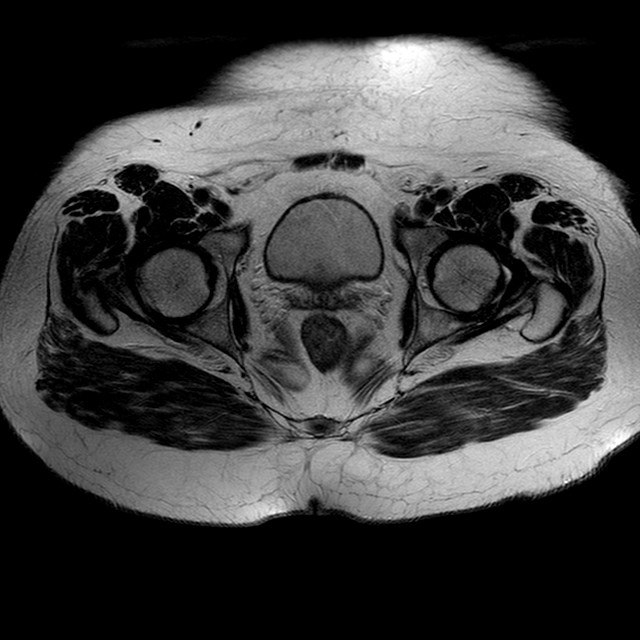

Esami: RMN BACINO

T2w TSE

Evidenti e simmetriche alterazioni osteofitosiche in regione coxo femorale con riduzione delle rime articolari. Degenerazione completa del cercine glenoideo. Non attuali segni di versamento articolare. Non segni di edema osseo che escludono attuale algodistrofia od osteonecrosi. Lieve e simmetrica riduzione del trofismo della muscolatura glutea.